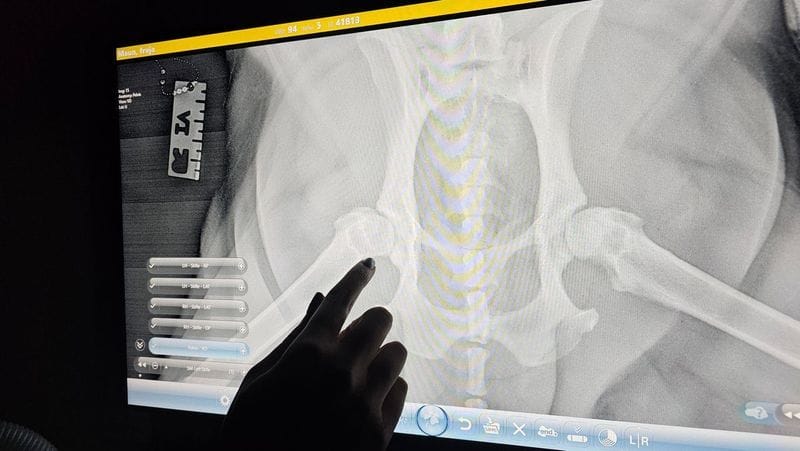

1. X-rays

X-rays are often the first step in diagnosing bone fractures, arthritis, and joint dysplasia. They provide a clear view of the bones and joints, allowing us to identify abnormalities and assess the severity of the issue.